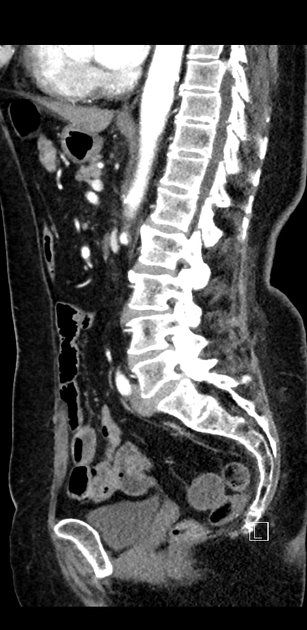

CT Bleeding Study

4 views

Jan 20, 2025

A patient presents with acute hypotension and hematochezia. An estimated 2L of blood loss was recorded in the ED. The patient was referred to general surgery. The bleeding stopped, and the patient remained hemodynamically stable. A colonoscopy was arranged. CT findings suggest an unusual cause of lower gastrointestinal bleeding. Based on the provided CT scan and case history, what is the most likely diagnosis?

Correct answer is Appendiceal hemorrhage due to angiodysplasia